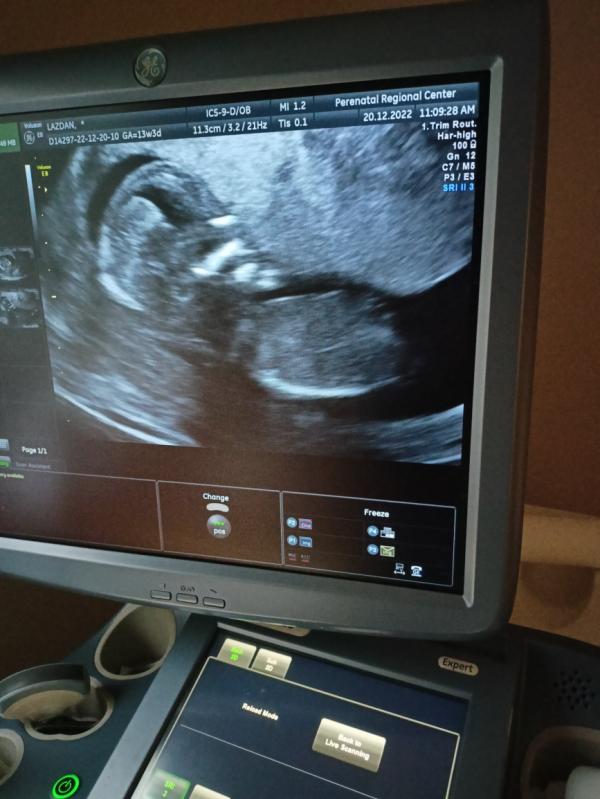

На УЗИ я вопросов не задавала, врач включила сердцебиение плода послушать, смотрела всё молча, в самом конце повернула ко мне монитор, показала малыша, голову, ручки, ножки, носик, позвоночник. Курносый, длинноногий) фото не распечатали, но разрешили сделать фото с экрана в конце) уже после я посмотрела в карте, что все показатели, измерения по норме. Врач Кожевникова. Пол не сказали. Хотя когда я час пыталась вызвать такси, чтобы ехать в перинатальный центр, и никто не находился, а потом приехал таксист по имени Илья (мы с мужем так сына хотим назвать), я подумала, что вдруг это знак😁